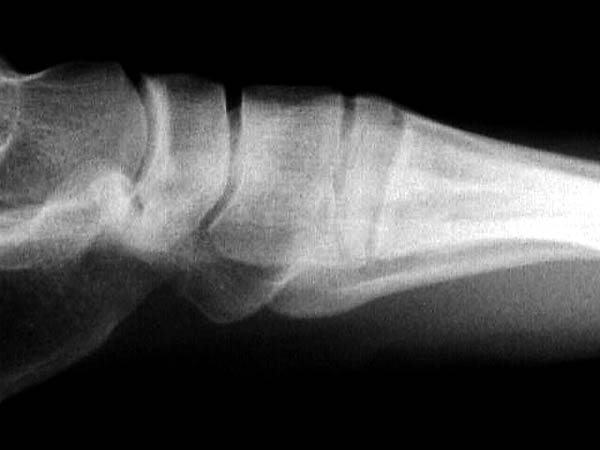

По снимкам нельзя исключить разрыв связки Лисфранка (связки между медиальной клиновидной костью и основанием второй плюсневой). Помогает в диагностике клиника (наличие изолированной гематомы на подошвенной поверхности стопы) и МРТ картина. Если связка повреждена - необходимо оперативное лечение.

По первому снимку, не видя больного, мог бы заподозрить перелом основания 3-й плюсневой кости. Поэтому избрал бы тактику консервативного лечения, как при переломе плюсневых костей без смещения!

Здесь КТ и сравнительные снимки стопы под нагрузкой.

Диагностировано повреждение медиальной и латеральной колонны.